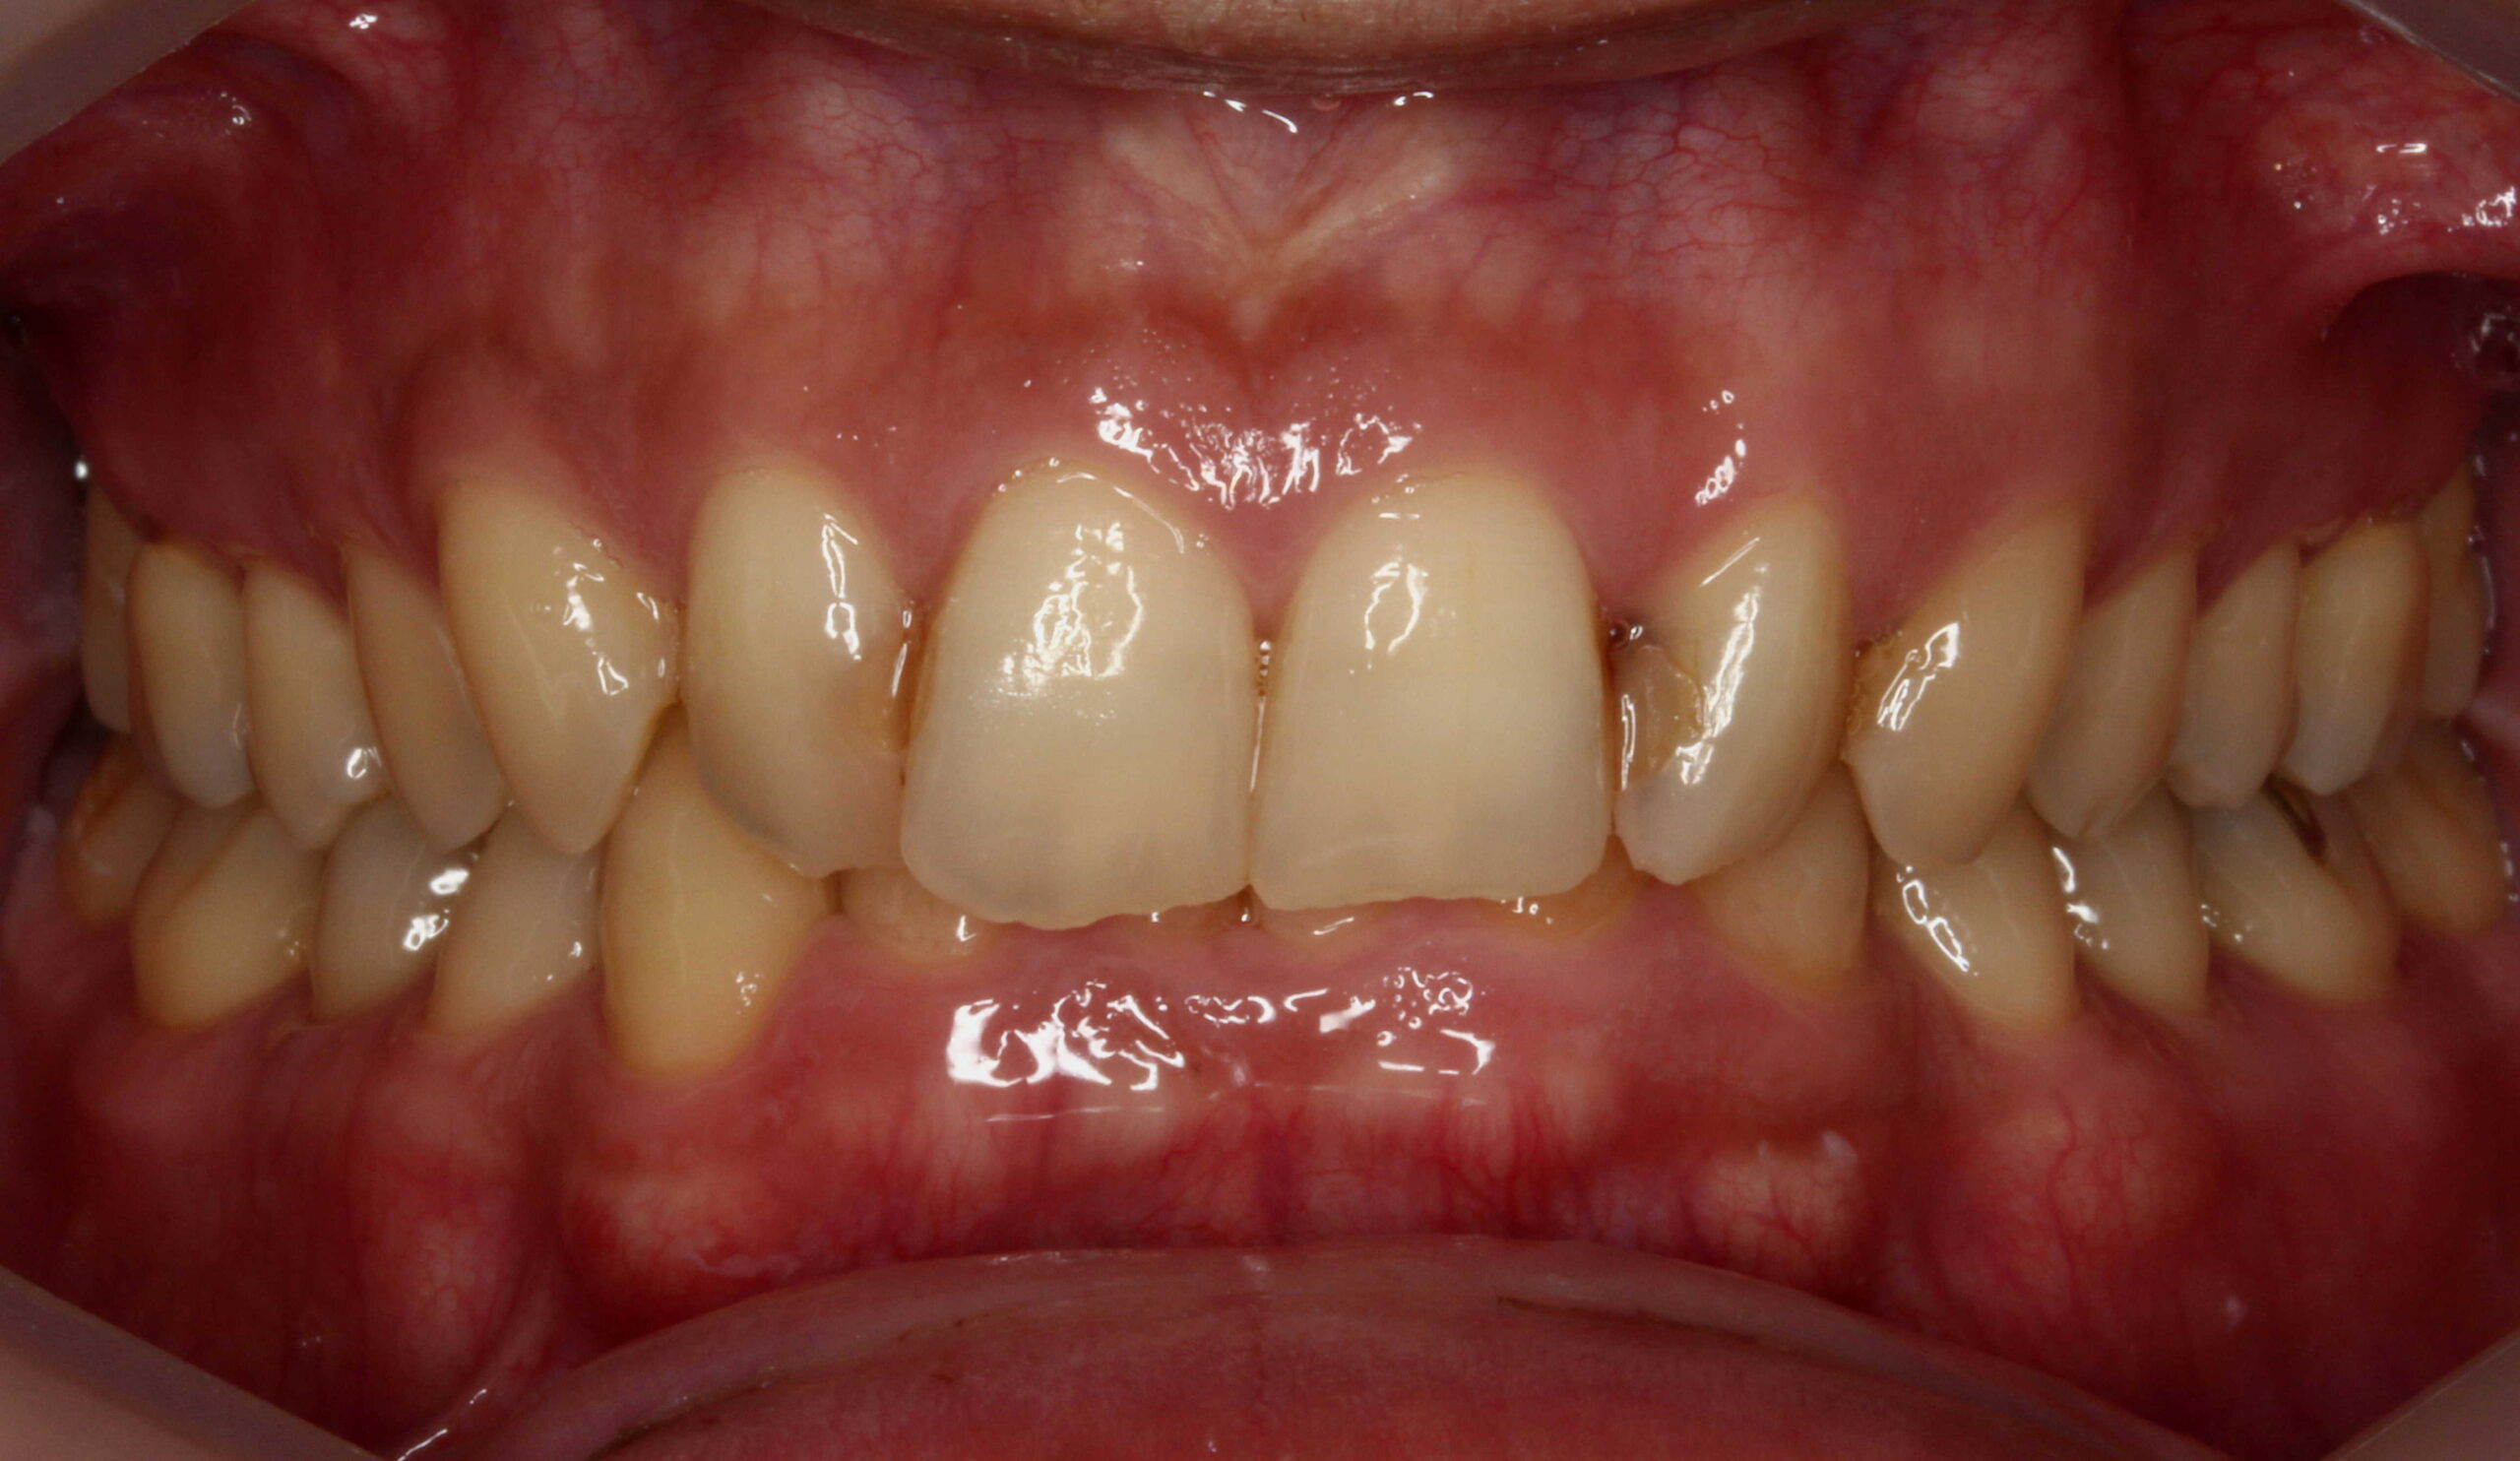

前歯6本の削らないラミネートベニア症例です。

前歯のレジン(プラスチック治療)が劣化し、継ぎ接ぎが目立っている方の症例です。

黄ばみと歯並びを削らないラミネートベニアでの治療希望でした。

この症例も削らないラミネートベニアに適しています。

レジンの継ぎ接ぎが目立っていたのと歯並びが改善されました。

全体的にもホワイトニングも行ったので、清潔感が出てお口元の印象が変わりました。